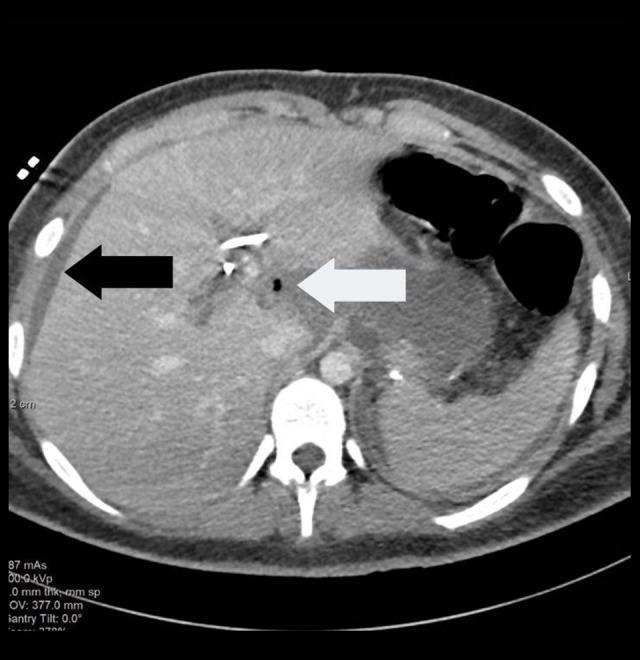

BACKGROUND Conservative management of blunt trauma to the liver is commonly used when there are no immediate signs of rupture or hemorrhage, but requires patient monitoring. The rate of failure for non-operative management ranges is 3-15%. This report is of a 21-year-old man with a previous history of gastrectomy, cholecystectomy, and biliary stenting with failed non-operative management of blunt trauma to the liver following a motor vehicle crash, due to traumatic stent perforation. CASE REPORT The patient reported abdominal pain and had positive FAST for fluid in the hepatorenal space. CT abdomen showed grade 3 hepatic injury and a common bile duct stent. He was resuscitated and admitted to the ICU. He developed escalating abdominal pain and tachycardia without hypotension. Repeat CT demonstrated a paraduodenal gas bubble. He underwent exploratory laparotomy, during which the following were found: hemoperitoneum, no active bleeding, a 3-cm blue stent exiting the left hepatic duct surrounded by a fibrous tract, and bile spilling from around the stent. The protruding portion of the stent was resected, the was tract oversewn, and the abdomen was closed. Once stabilized, the patient underwent ERCP with removal of the remaining stent segment. The postoperative course was complicated by surgical wound infection and fascial dehiscence managed operatively and with local wound care, and deep-space infections managed by interventional radiology drainage. CONCLUSIONS Blunt trauma injury of the liver can be successfully managed conservatively. However, this case highlights the importance of knowledge of the patient's medical history and the presence of biliary stents, which can result in traumatic biliary perforation with an intact liver.

患者报告腹痛,超声检查显示肝肾间隙有液体,腹部 CT 显示 3 级肝损伤和胆总管支架。他接受了复苏治疗并收入 ICU。他出现了进行性腹痛和心动过速,但没有低血压。再次 CT 显示十二指肠旁气肿。他接受了剖腹探查术,术中发现:腹腔积血,无活动性出血,一根 3 厘米长的蓝色支架从左肝管穿出,周围有纤维通道,支架周围有胆汁溢出。切除突出的支架部分,缝合通道,关闭腹部。一旦病情稳定,患者接受了 ERCP 以取出剩余的支架段。术后病程复杂,包括手术切口感染和筋膜裂开,通过手术和局部伤口护理进行治疗,以及通过介入放射学引流治疗深部感染。